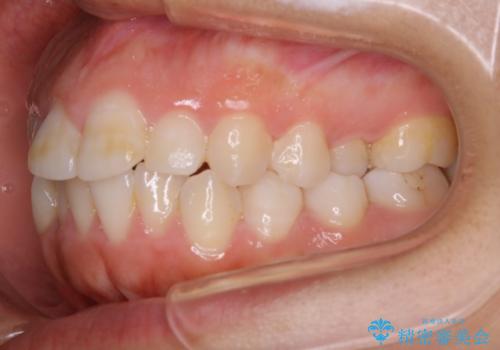

- 口元を下げたいという主訴でご来院されました。

ガタつきの度合いは軽度でしたが歯列の幅が狭く、その分前歯が上下とも前方に出てしまっていました。

しっかりと口元・顔貌まで変化を起こせるように上下左右の第一小臼歯を抜歯し、ワイヤー装置にて矯正を開始することとなりました。

抜歯矯正

叢生(ガタつき)が強い場合や上下もしくはどちらかの歯が前方に出ている場合、その問題を解決するためのスペース作りのため抜歯をすることがあります。

多くのケースは第一小臼歯を抜歯することで並べたい前歯のすぐ近くにスペースを作りガタつきや出っ歯を改善していきます。